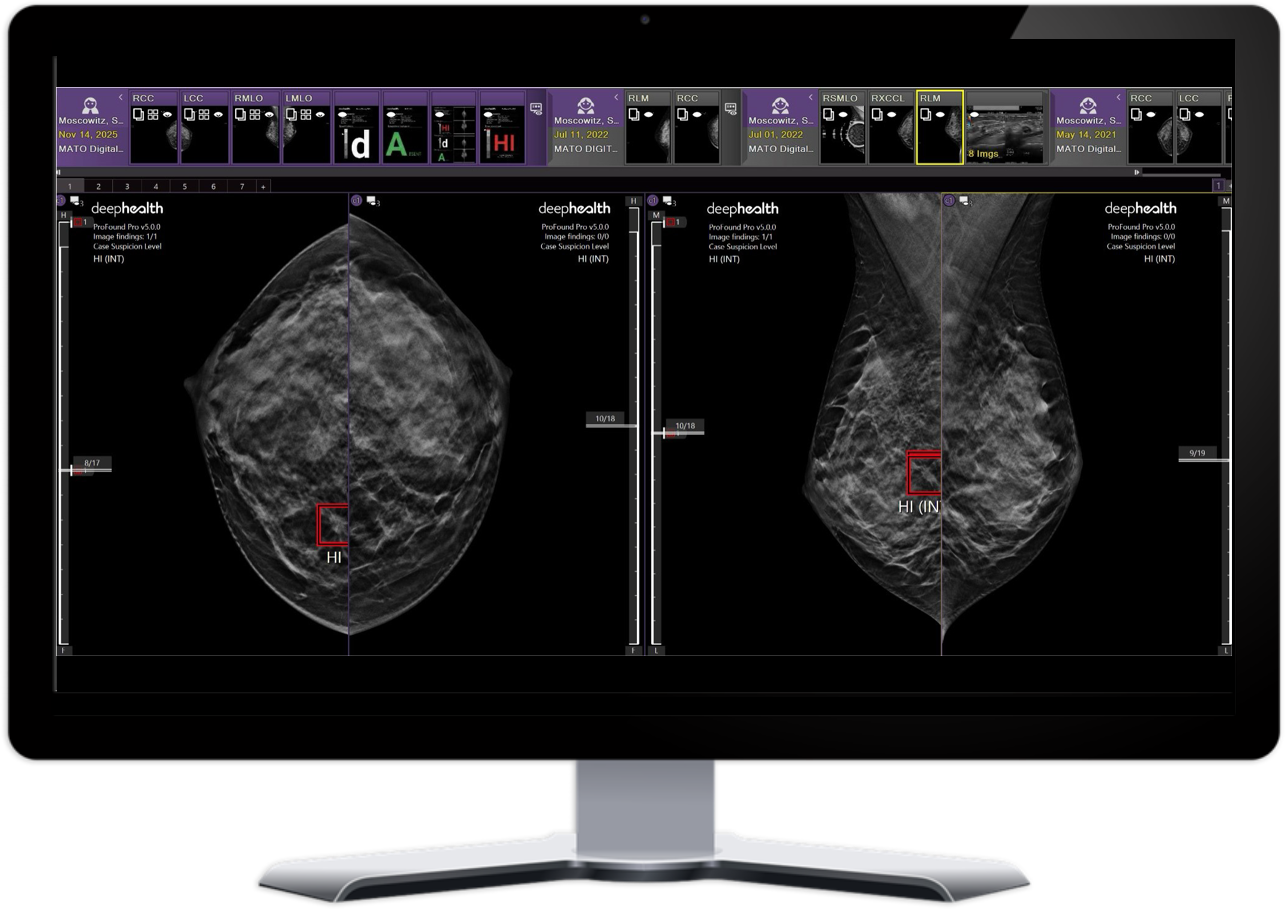

Enables more accurate diagnosis1,2 with the use of priors3 and automatic localization of regions of interest and degree of suspicion

Improves turnaround time by indicating cases based on suspicion level and rapidly flagging high-suspicion exams within minutes, reducing delays and enabling timely same-day follow-up.

AI-powered Safeguard review workflow

Improves cancer detection rate with second reviewer workflow, decreasing false negatives and emphasizing likely missed cancers, including hard-to-detect ones. 2, 7, 8